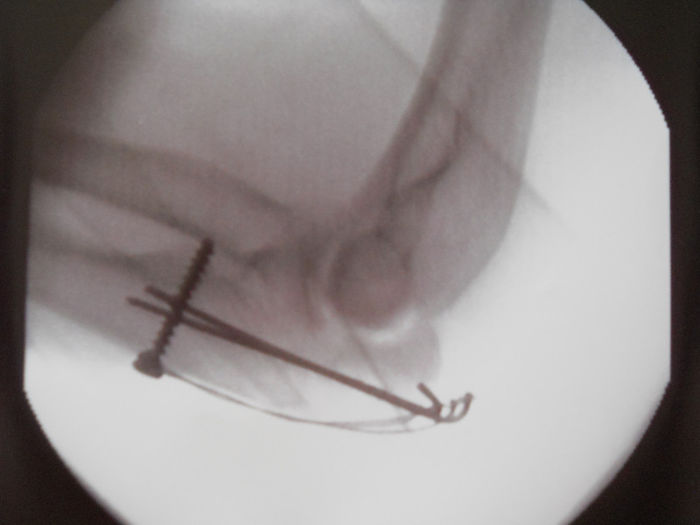

Merci pentru compassion! Durerea s-a mai atenuat, mă descurc însă cam greu cu o mână p'aci singură. Luni îmi scoate firele, peste alte două săptămâni fix de ziua mea, scap și de ghips, de restu' numa' la anu'. Fac o poză să vezi ce sfredel și droturi mi-au montat ăștia în cioante :))